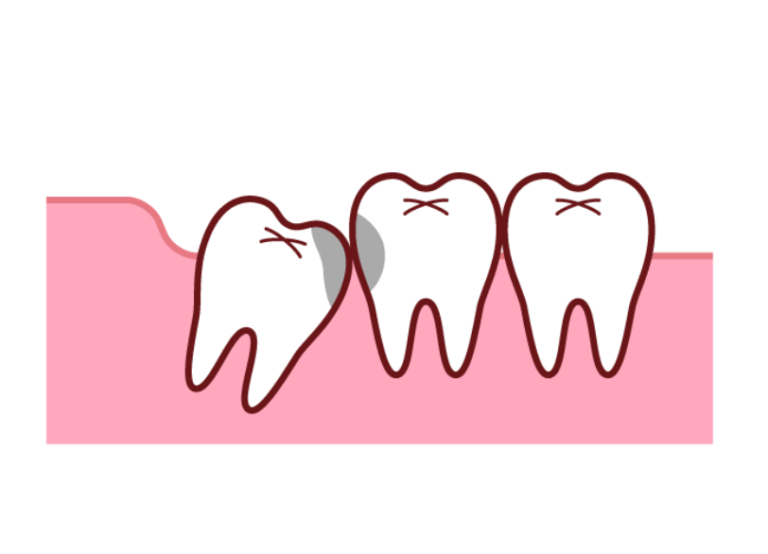

親知らずが斜めに生えていると、その手前にある非常に大切な「第二大臼歯」との間に複雑で深いすき間ができてしまいます。 この部分は歯ブラシの毛先が絶対に届かないため、極めて汚れが溜まりやすく気づかないうちに、親知らずだけでなく手前の健康な第二大臼歯までが大きなむし歯になってしまうリスクが非常に高いのです。